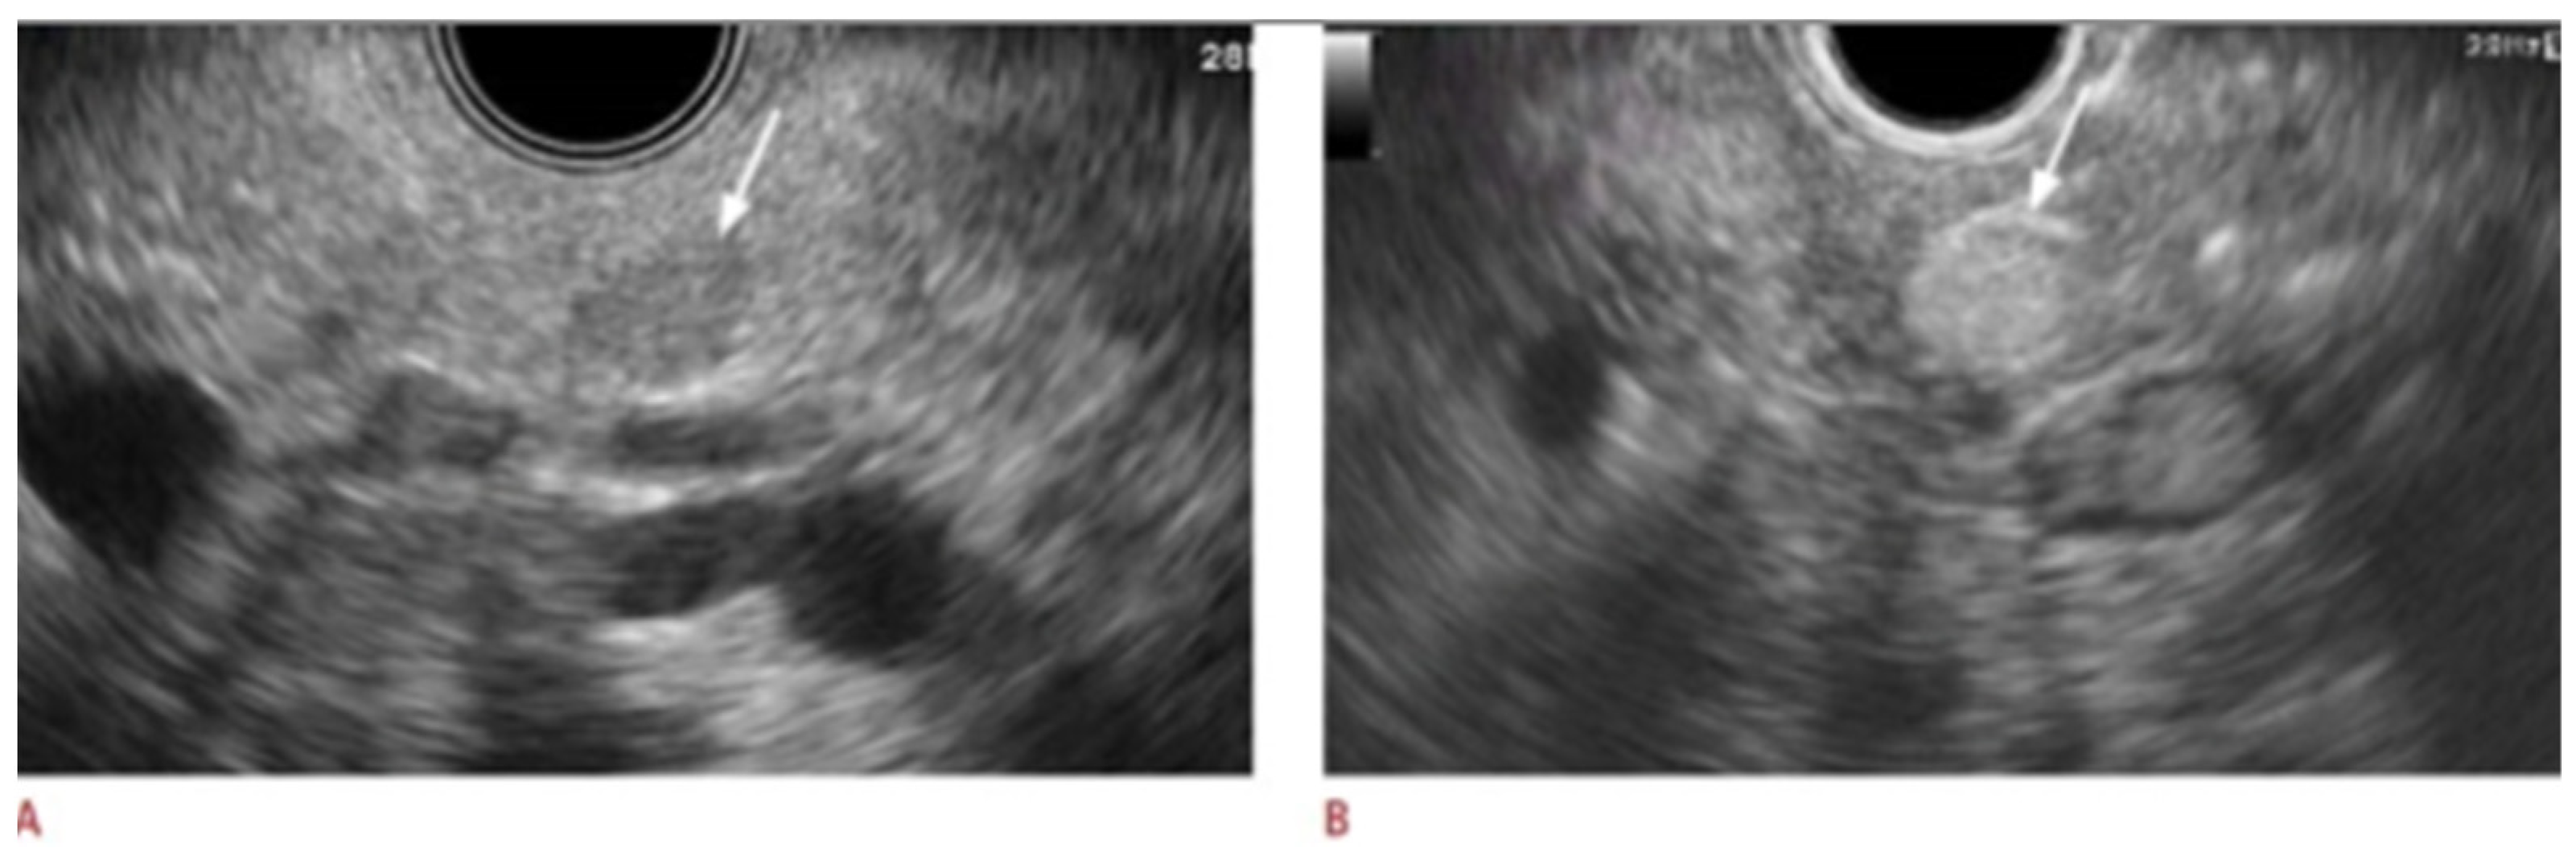

- Yamashita, Y.; Kitano, M. Endoscopic Ultrasonography for Pancreatic Solid Lesions. J. Med. Ultrason. 2001 2020, 47, 377–387. [Google Scholar] [CrossRef] [PubMed]

| Pancreatic Adenocarcinoma [26,42,43] | Heterogenous, hypoechoic mass with an irregular border | High | Variable |